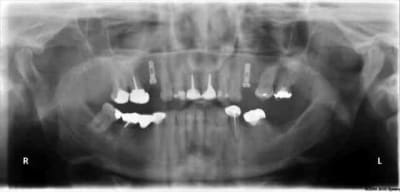

tiens...un ptit cas...

ok, c'est un mini soulevé...mais bon , c'est un exemple...

juste une précision...premier foret 1.3mm sur 8mm...expansion pour mettre un implant de 4x10...

j'ai juste "léché" la préparation du site final avec le foret terminal du système...sur 8mm...avant d'insérer l'implant...stab primaire au top...blocage à 40 Ncm...

rien...une cloison du sinus...;-))

???? tu as un pano ou un scan je ne situe pas ça comme une cloison, mais je vois mal.

j'ai la pano au cab...pas de problème...çà peut aussi être un épaississement de la membrane dans ce cloisonnement...il a eu un bon rhume quelques semaines avant...